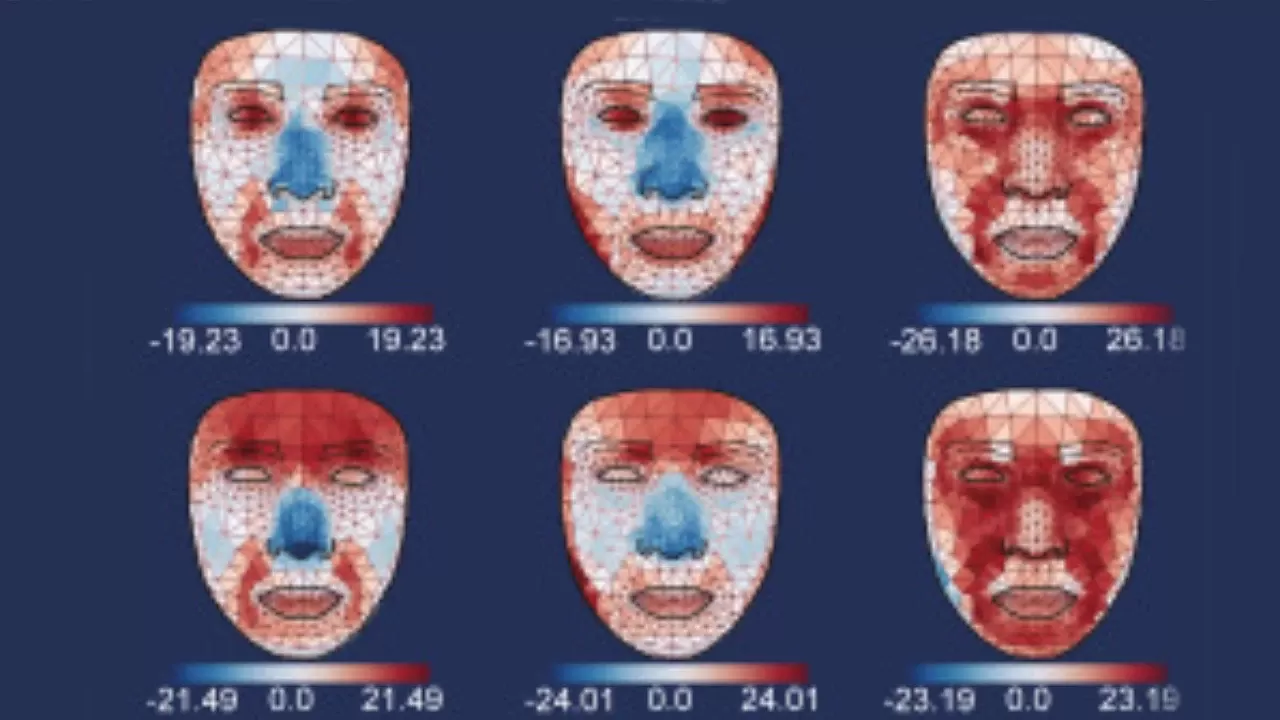

NTV'nin aktardığı habere göre; araştırmacılar, yaklaşık 2 bin 800 Çinli katılımcının yüzlerinin termal fotoğraflarını çekerek 54 farklı noktada sıcaklık analizi yaptılar. Ulaşılan veriler ile eğitilen yapay zeka modeli, katılımcıların biyolojik yaşlarını sıcaklık değişimlerine göre tahmin etmekte kullanıldı. Özellikle burun ve yanakların soğumasının yaşlanmayla ilişkilendirildiği gözlemlendi.

Çalışma, diyabet ve karaciğer hastalığı gibi metabolik bozuklukların, göz çevresinde sağlıklı bireylerle kıyaslandığında daha yüksek sıcaklıklara neden olduğunu ortaya koydu. Bu bulgular, termal yüz görüntülemenin hastalıkların erken teşhisi için potansiyel bir araç olabileceğini gösteriyor.